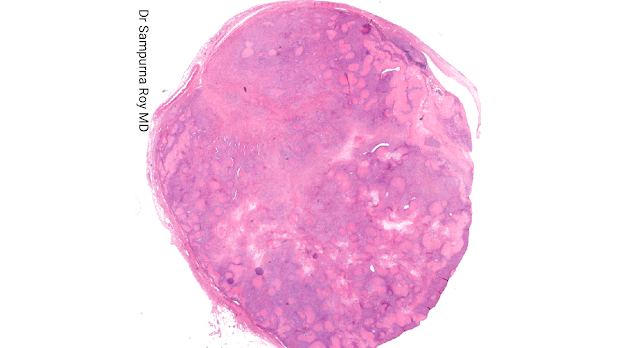

Dermatopathology Case 202

45-year-old female who presented with a slow-growing painless swelling over the back of the thigh that had been present for 4 years. Answer

Self Assessment Cases in Dermatopathology: Editor: Dr Sampurna Roy MD INDIA